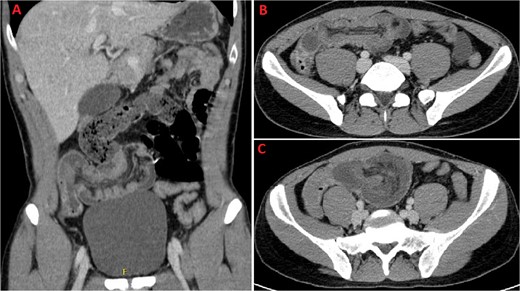

A 31-year-old male was complaining episodes of abdominal pain in the umbilical region with nausea. In medical history he underwent an appendectomy. Chronic gastritis was found on esophagogastroduodenoscopy (EGD) and proton-pump inhibitors (PPI) treatment was started, with regression of symptoms. After two months, he took ketoprofen for back pain for two days when a severe abdominal pain in the umbilical and right iliac region started, with nausea and vomit. He had normal vital signs and tenderness in the right lumbar and iliac regions. Blood exams showed leucocytosis (GB 14.120 × 106/ml) with neutrophilia (88%). A plain abdomen X-ray showed absence of representation in the right regions, with small bowel loops’ distension on the left (Fig. 1). An abdomen US displayed the presence of visceral distension with cockade appearance, consistent with an inflammatory condition of the cecum and the ileocecal site, with wall thickening of 6 up to 10 mm and free fluid near the cecum (Fig. 2). Contrast-enhanced CT confirmed wall thickening of the last ileal loop and the cecum up to 20 mm (Fig. 3A and B). Antibiotic therapy was started. The next day the pain worsened and there was an abdominal mass in the right iliac region with rebound tenderness. Blood examination showed further increase in leucocytosis (GB 18560) and a new CT was done. The wall thickening increased up to 24 mm, and the last ileal loop was more hypointense, with a twisted appearance around its mesentery (Fig. 3C). Exploratory laparotomy was performed. During surgery we found an ileal intussusception of the distal ileum near the cecum, and an ileocecal resection with ileo-colic anastomosis was done. On the first post-operatory day he developed haematochezia and acute anaemia, so he underwent reintervention with resection of the anastomosis and ileostomy. The following post-operative course was uneventful.

A and B: Coronal and axial sections of contrast-enhanced CT scan confirming wall thickening of the last ileal loop and the cecum up to 20 mm. C: CT imaging performed the following day, displaying increased wall thickening up to 24 mm with the last ileal loop appearing twisted around its mesentery.